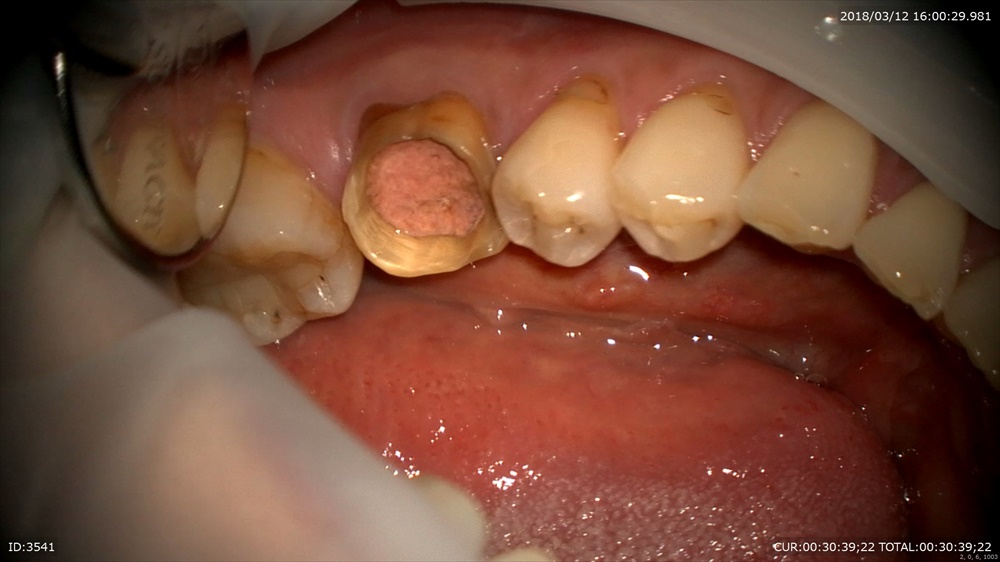

右側は痛みを訴え来院時。歯茎から膿が飛び出しています。

左は今日。何もなくなりました。

今日 スタート時2月

症状も消えました。